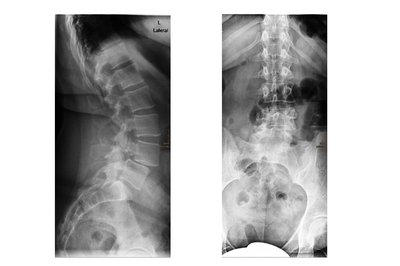

• Röntgenbild Wirbelgleiten

Wirbelgleiten zwischen dem 4. und 5. Lendenwirbel (Spondylolisthese L4/5)